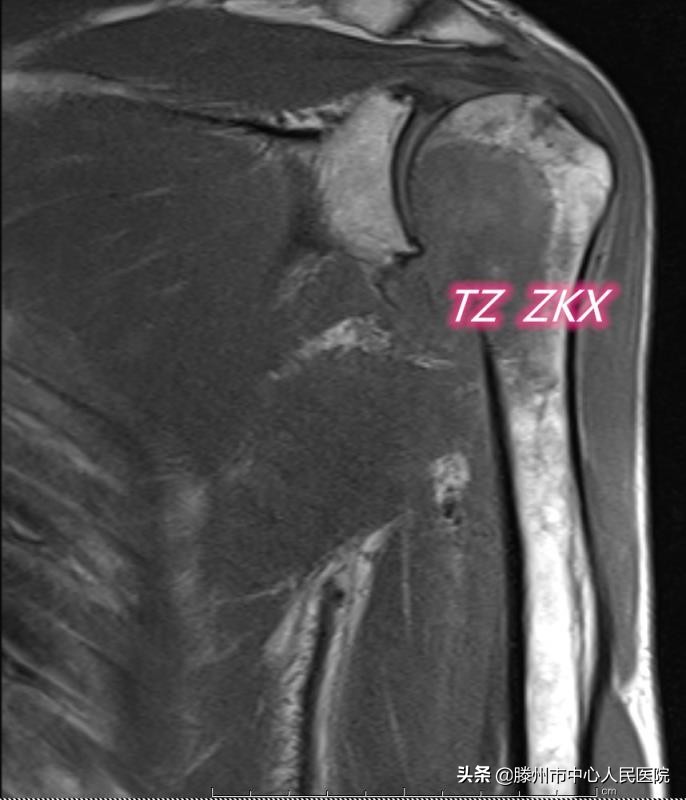

患者71歲,2019年12月診斷胃底-賁門癌并縱膈、腹膜后淋巴結(jié)多發(fā)性轉(zhuǎn)移,經(jīng)過6個周期藥物治療,病情穩(wěn)定。3月前出現(xiàn)左側(cè)肩胛部疼痛,逐漸加重,上肢活動受限,CT及MRI顯示左側(cè)肱骨頭及肱骨上段溶骨性轉(zhuǎn)移,骨皮質(zhì)破壞范圍超過1/2,隨時都有發(fā)生病理性骨折的可能,一旦發(fā)生病理性骨折,必將嚴(yán)重影響患者的生活質(zhì)量。骨科會診考慮患者高齡,伴有其他多部位轉(zhuǎn)移,不適合手術(shù)治療,建議微創(chuàng)治療。張開賢主任醫(yī)師團(tuán)隊(duì)在借鑒既往多年骨轉(zhuǎn)移瘤微創(chuàng)治療經(jīng)驗(yàn)的基礎(chǔ)上,經(jīng)過多次討論,決定實(shí)施CT引導(dǎo)微波消融聯(lián)合介入內(nèi)固定及骨水泥成形術(shù)。